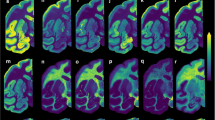

The pronounced cytoprotective action of parkin sulfhydration as well as the reciprocal relationship of parkin’s nitrosylation and sulfhydration suggest that alterations of sulfhydration participate in the pathophysiology of PD. In accordance, we monitored sulfhydration and nitrosylation in the striatum of PD patients (Fig. 4 and Supplementary Fig. 7). We confirm the increase of parkin nitrosylation in PD brain,3 and also observe a 60% decrease in parkin sulfhydration in patient brain.

(a) The maleimide technique demonstrates that parkin sulfhydration is depleted in the striatum of PD patients. (b) Nitrosylation of parkin is increased in PD patient brain. *P<0.02 by one-way analysis of variance (ANOVA; n=7 control and n=6 PD samples for (a)); **P<0.01 by one-way ANOVA (n=5 each control and PD for (b)). All data are expressed as mean±s.e.m.